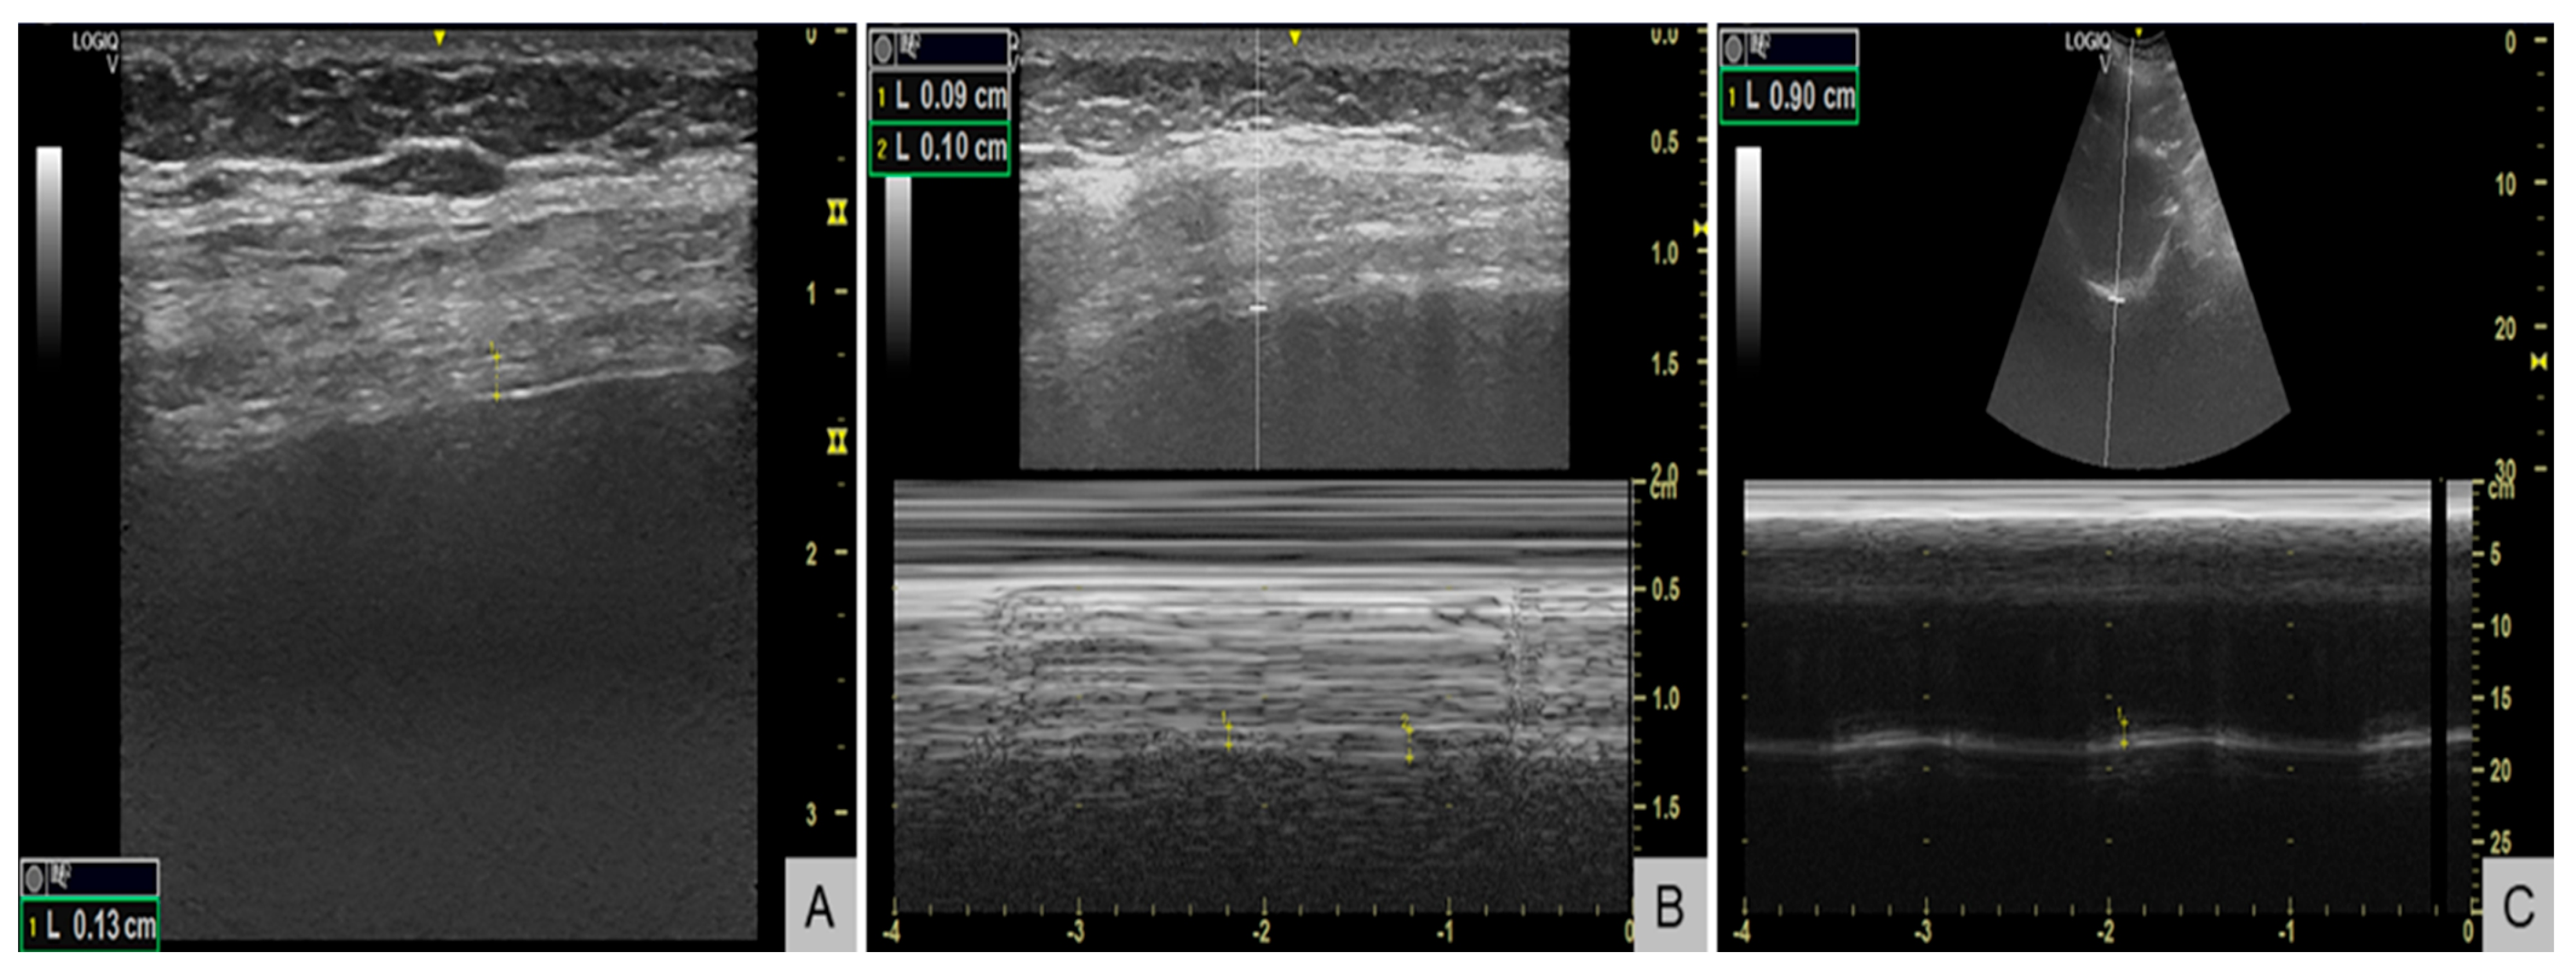

Respiratory evaluation also identified significant respiratory muscle weakness. Maximal inspiratory pressure (MIP) was −38 cmH2O (normal <−80 cmH2O in women), maximal expiratory pressure (MEP) +55 cmH2O (normal >100 cmH2O), and sniff nasal inspiratory pressure (SNIP) 34 cmH2O (normal >70 cmH2O), all below the lower limits of normal. Diaphragm ultrasound (Figure 3) revealed end-expiratory thickness 0.9 mm (right) and 1.3 mm (left) (normal for women >1.7–2.0 mm) (Figure 3A), thickening fraction 11% (right) (Figure 3B) and 16% (left) (normal >20%), and inspiratory excursion < 1.0 cm (Figure 3C) bilaterally (normal for women >1.5 cm during quiet breathing), consistent with diaphragmatic weakness. Polysomnography showed an apnea–hypopnea index of 13 events/hour, predominantly central hypopneas (n = 12), with a nadir oxygen saturation of 86% and no obstructive events. The patient’s body mass index was 23 kg/m2.

Figure 3. Diaphragm ultrasound demonstrating diaphragmatic weakness. (A) B-mode image showing reduced end-expiratory diaphragm thickness of 1.3 mm in the left hemidiaphragm (normal for women >1.7-2.0 mm). (B) M-mode image showing a reduced thickening fraction of 11% in the right hemidiaphragm (normal >20%). (C) M-mode tracing showing reduced inspiratory excursion of 0.9 cm (normal for women >1.5 cm during quiet breathing).